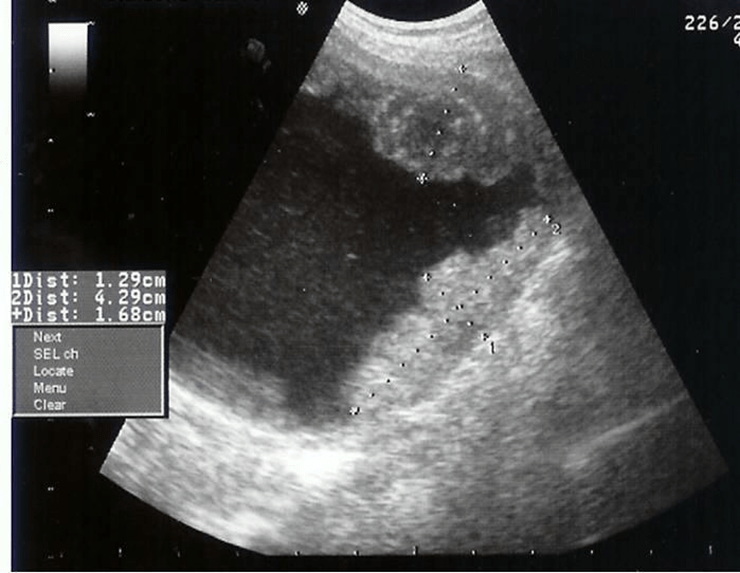

Name the two pathologies in this image.

What is a bladder stone within a diverticula?